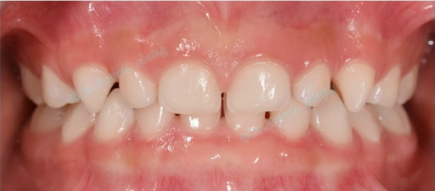

牙缝稀稀拉拉,原来是缺了几颗牙

有些小朋友牙缝很大,是因为牙齿数目不足,也就是先天缺牙。先天缺牙有遗传倾向少数情况跟全身疾病相关

图片

乳牙的先天缺牙一般不需要干预,恒牙先天缺牙如果影响咀嚼或美观,建议检查后根据具体情况决定是否需要处理。

不过并不是牙缝稀稀拉拉的小朋友都有缺牙的情况,比如大多数乳牙列都是有一些散在牙缝的,这是正常现象,家长们不必太紧张。

健康的乳牙列有散在生理间隙